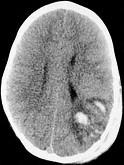

- 单项选择题男,3岁, 头颅被球击中,请结合CT图像, 选择最可能的诊断是 ( )

A、高血压性脑出血

B、脑结核

C、脑挫裂伤血肿形成

D、动脉瘤破裂出血

E、血管畸形